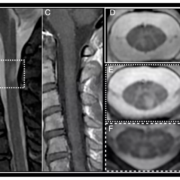

A study assessed the effect of an intensive initial IOP lowering treatment strategy on the progression of visual field damage. A total of 242 patients with newly detected early or moderate untreated open-angle glaucoma were enrolled at two university hospitals in Sweden. Participants were randomly allocated (1:1) to either initial treatment with intensive IOP-lowering medications followed by 360° laser trabeculoplasty (LTP), or to traditional mono-therapy, which was increased when deemed necessary. The primary study outcome of interest was the predicted remaining visual field, as measured by the visual field index (VFI) at projected end of life. Results: The median untreated IOP was 24 mmHg in both treatment groups. During follow-up, median and mode IOP was 17 mmHg in the mono- and 14 mmHg in the multi-treated group. In the mono-treated group the median VFI at projected end of life was 79.3%, and in the multi-treated group 87.1%, p=0.15. Annual rate of progression of visual field damage was faster in mono-treated than in multi-treated participants; median losses per year were 0.65 and 0.25 percentage units respectively, p=0.09. Progression events occurred in 21% of the mono- and in 11% of the multi-treated participants, p=0.03. Adverse events, mostly mild, were reported in 25% of the mono-, and in 36% of the multi-treated participants. Differences in visual field outcomes between treatment groups were more pronounced in participants having higher baseline IOP defined by median split of untreated IOP values. In the overall analysis the visual field outcomes were not overwhelming better in the multi-treated group, but post-hoc analysis showed definite benefit in patients with higher untreated IOP. Based upon the results of this study, initial intensive treatment may be considered in glaucoma patients with high untreated IOP at diagnosis, while we found no evidence that multi-therapy should be given routinely to all glaucoma patients.